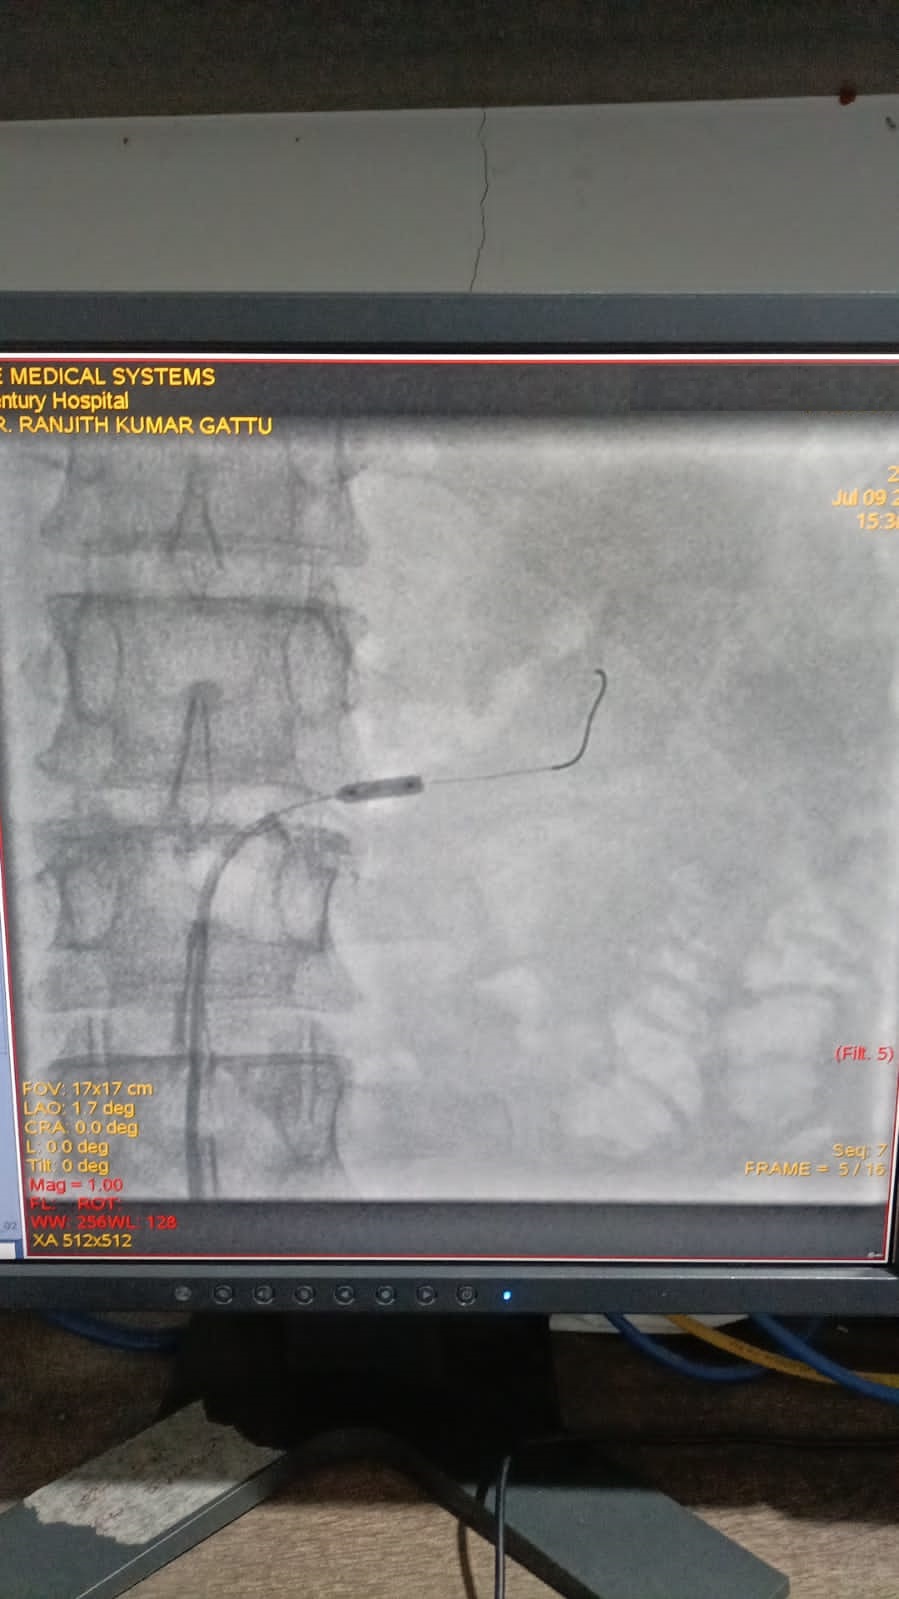

Has done more than 10000 cardiac and peripheral Cath lab interventions

Interventional Cardiologist - 10+ years of experience in cardiology